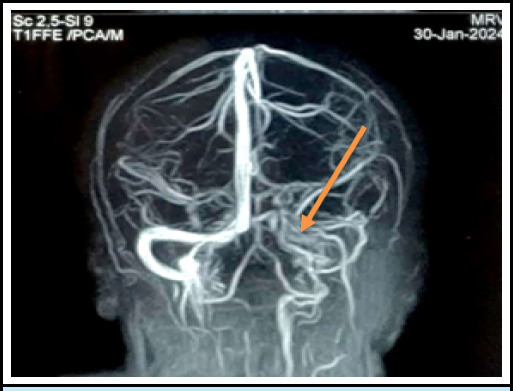

Pregnancy is the pro-thrombotic state. The objective of this report is to highlight the rare occurance of postpartum cavernous sinus thrombosis associated with eclampsia and gestational diabetes mellitus, emphasizing its clinical presentation. A 25-year-old Muslim female came with the complaint of headache,post auricular and right parietal region on 8th day post-partum. She had a history of postpartum eclampsia and Gestational Diabetes Mellitus for which she was treated with magnesium sulfate and oral hypoglycaemic agents respectively. MRV showed a filling defect in right transverse sinus, sigmoid sinus, and internal jugular vein. She was then admitted to the ward and was treated with heparin and antibiotics. She was then discharged on oral rivaroxaban. As pregnancy is itself a state of hyper-coagulable state, there seems to be a significant thrombosis risk. Hence clinicians should be aware of the possible thrombotic disorder in the background of this vignette.

妊娠是促血栓形成的状态。本报告的目的是强调产后海绵窦血栓形成合并子痫和妊娠糖尿病的罕见发生,并强调其临床表现。25岁穆斯林女性,产后第8天主诉头痛、耳后及右顶骨区。患者有产后子痫和妊娠期糖尿病病史,曾分别给予硫酸镁和口服降糖药治疗。MRV显示右横窦、乙状窦及颈内静脉充盈缺损。随后,她住进了病房,接受了肝素和抗生素治疗。她随后口服利伐沙班出院。由于妊娠本身就是一种高凝状态,因此似乎存在明显的血栓形成风险。因此,临床医生应该意识到在这个小插曲的背景下可能的血栓性疾病。